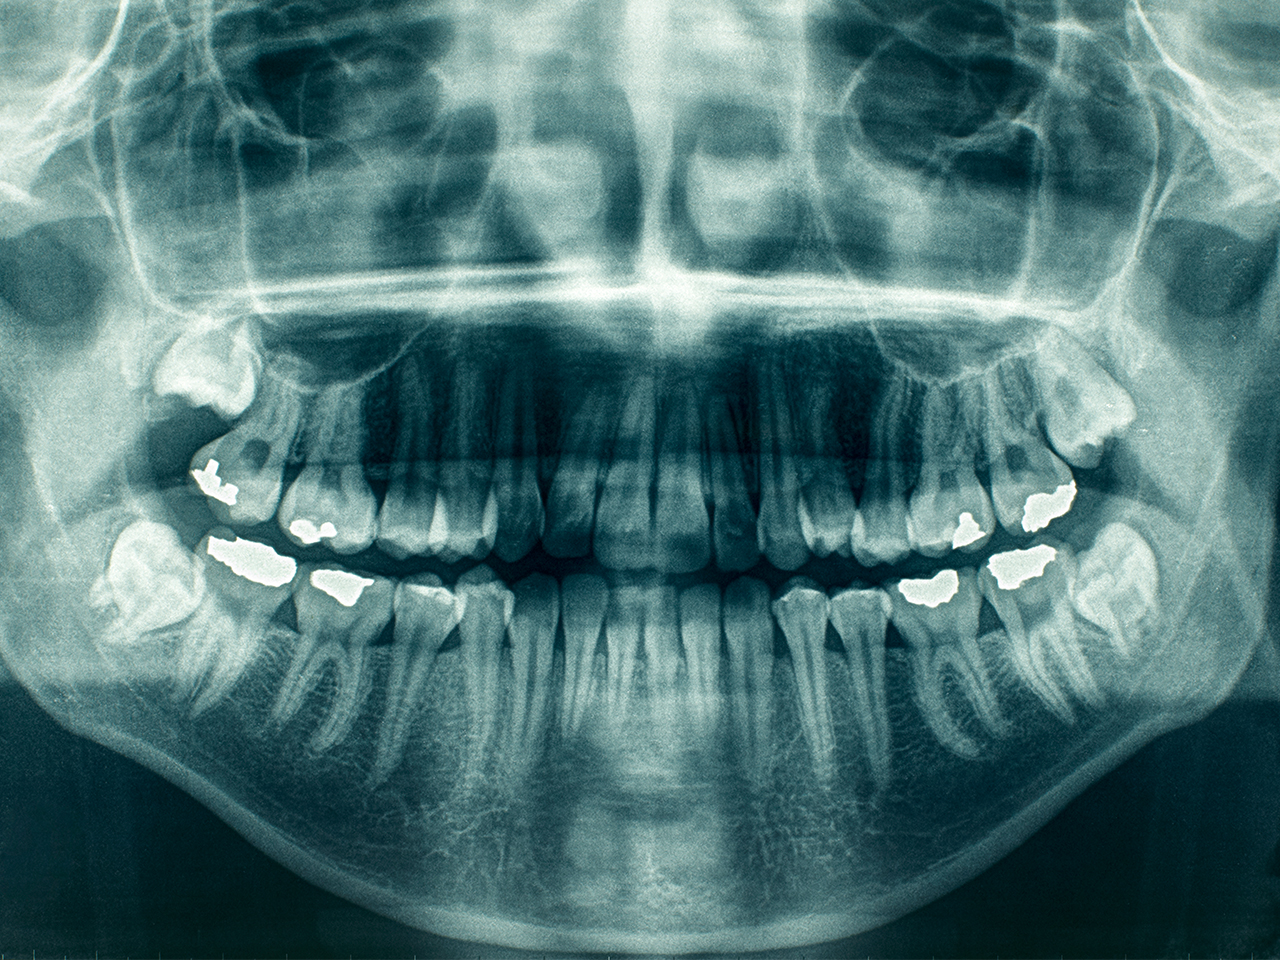

Si pensi alla radiologia: i raggi X rappresentano gli strumenti necessari che permettono al dentista di vedere quello che non è visibile a occhio nudo, quello che si nasconde dietro patologie insospettabili, per capire dove si annida il problema per risolverlo in modo efficace.

La radiologia è un aspetto della diagnostica che ha la prerogativa di permettere al dentista di imboccare la via giusta e sicura nella cura; per questo i dentisti italiani risultano essere in prima linea.

Da alcuni anni nello Studio Dentistico D'Orazio Francesco, sono presenti apparecchiature molto avanzate per quanto riguarda la radiologia, infatti questi strumenti ad alta definizione permettono di effettuare la diagnosi tridimensionale di un solo dente, dell’arcata dentale e anche di tutta la testa, se necessario.

La radiologia green non nociva per l'uomo

Le apparecchiature Green Ct di cui lo

Studio è dotato, sono quelle di ultima generazione che, in pochi secondi, permettono la diagnosi tridimensionale per poter diagnosticare immediatamente il problema all'interno del nostro studio odontoiatrico.

Grazie all’efficacia di Green Ct in radiologia, ci sono molti vantaggi concreti per i pazienti:

- un esame sicuro, garanzia di un’ottima diagnosi;

- una dose di raggi X pari al 20% in meno rispetto ad esami con altri tipi di apparecchiature;

- un esame immediato, poiché viene effettuato subito e dura solo 5,9 secondi;

- un grande comfort, poiché l’esame viene svolto in piedi senza alcun tipo di complicazione.